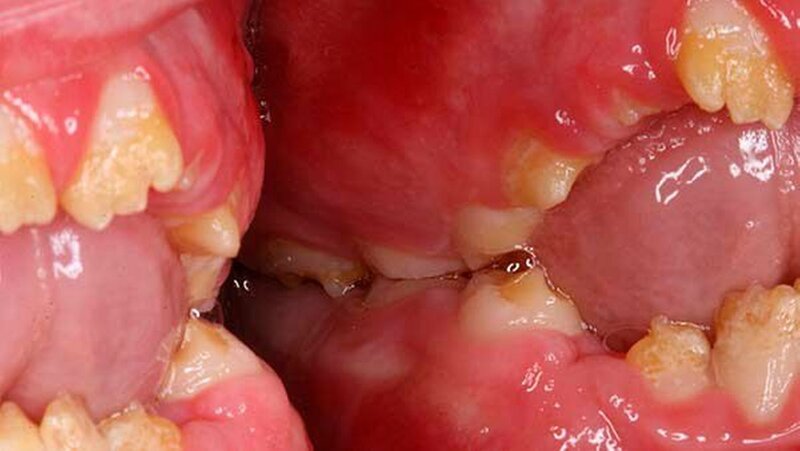

Im radiologischen Befund konnte teilweise ein Kontrast zwischen Schmelz und Dentin festgestellt werden, jedoch war bei beiden Dentitionen eine verminderte Schmelzdicke ersichtlich (Abbildung 4). Auf Grund der radiologischen und klinischen Beurteilung konnte die Diagnose Amelogenesis imperfecta generalisata vom hypoplastischen Typ gestellt werden.